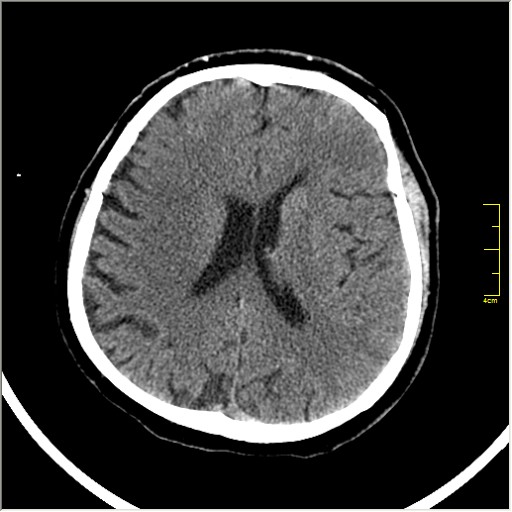

Пациентка Д. 64 года. Поступила с диагнозом ОНМК ???, жалобы на онемение и слабость в левой половине тела.

Ответ: Обратите внимание на правую среднемозговую артерию (MCA); М1 сегмент гиперденсен; сравните с другой стороной.

Этот признак называется [Dense MCA sign]; за счёт наличия тромбоза в её просвете. Этот признак является одним из ранних указующих КТ признаков при ишемическом инфаркте головного мозга. Более подробно об этом вы можете прочитать здесь: http://www.radiologyassistant.nl/en/483910a4b6f14.